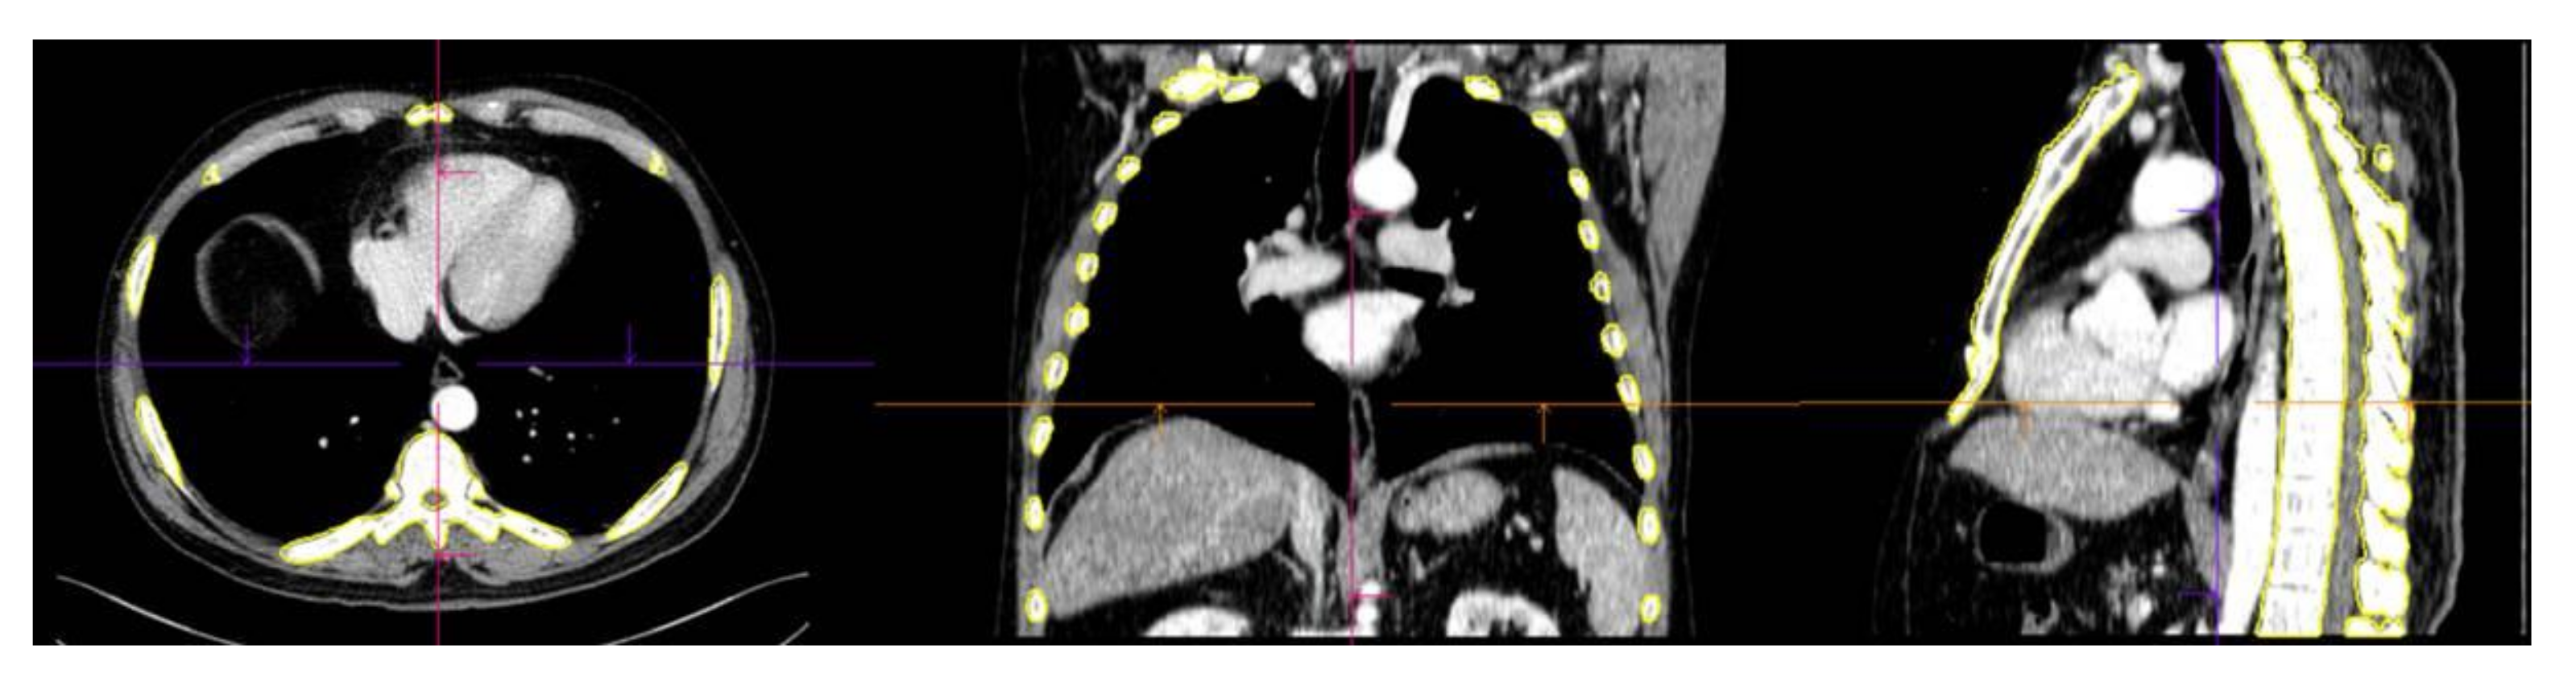

2.3. Lesion Segmentation and Radiomics Feature Extraction

Image segmentation and feature extraction were performed on contrast-enhanced chest CT scans using a prototype software program (syngo.via Frontier, version 1.2.2, Siemens Healthineers, Munich, Germany). Segmentation of the entire skeleton (including the spine, rib cage, sternum, clavicles, and scapulae) was performed using an automatic lesion segmentation tool within the software (Figure 2). The radiomics features of the segmented volume of interest (VOI) were extracted using the publicly available PyRadiomics library (PyRadiomics library, version 3.0.1. Available online: https://githumb.com/Radiomics/pyradiomics (accessed on 25 Mar 2021)). To correct the variability that resulted from parameters related to voxel size, the segmented volume of interest (VOI) was resampled to isometric voxels of 1 × 1 × 1 mm3 [20]. The radiomics features of the resampled images were extracted using the publicly available PyRadiomics library (R statistical software, version 3.5.2, Vienna, Austria. Available online: https://cran.r-project.org/bin/windows/base/old/3.5.2/ (accessed on 12 May 2021)). Radiomics features were subdivided into the following classes: first-order features (18 features), volume and shape features (14 features), texture-based features (68 features), wavelet-filtered features (688 features), and Laplacian of Gaussian-filtered features (430 features). One radiologic technologist (K.E.L.) performed image segmentation and feature extraction under the supervision of a radiologist (S.Y.L.).

An automatic lesion segmentation tool for the skeleton in the software was used to calculate the VOI for the spine, rib cage, sternum, clavicles, and scapulae.

Figure 2. Segmentation of the axial skeleton.